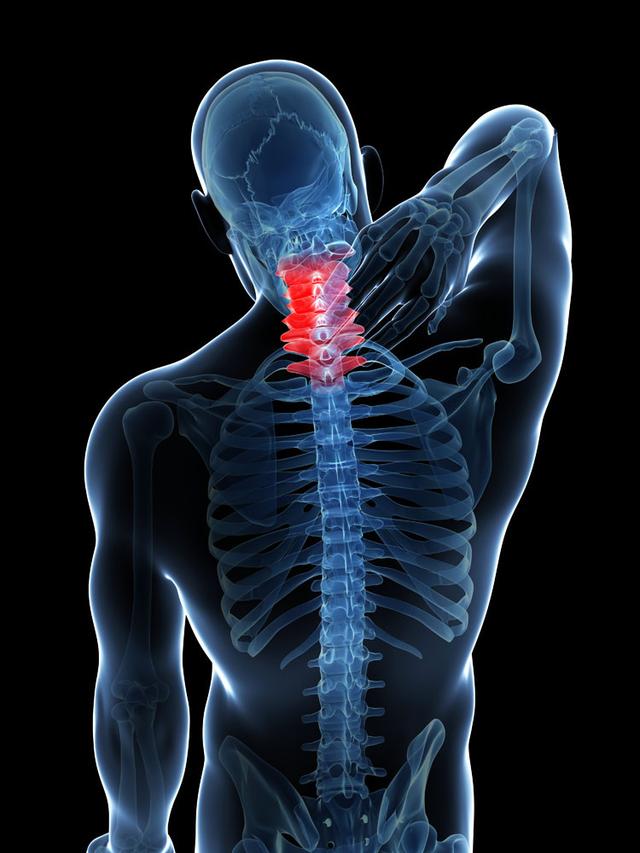

从一方面来说,人类是弱小的,容易生病,容易受伤,但从另一方面来说,人类也是强大的...